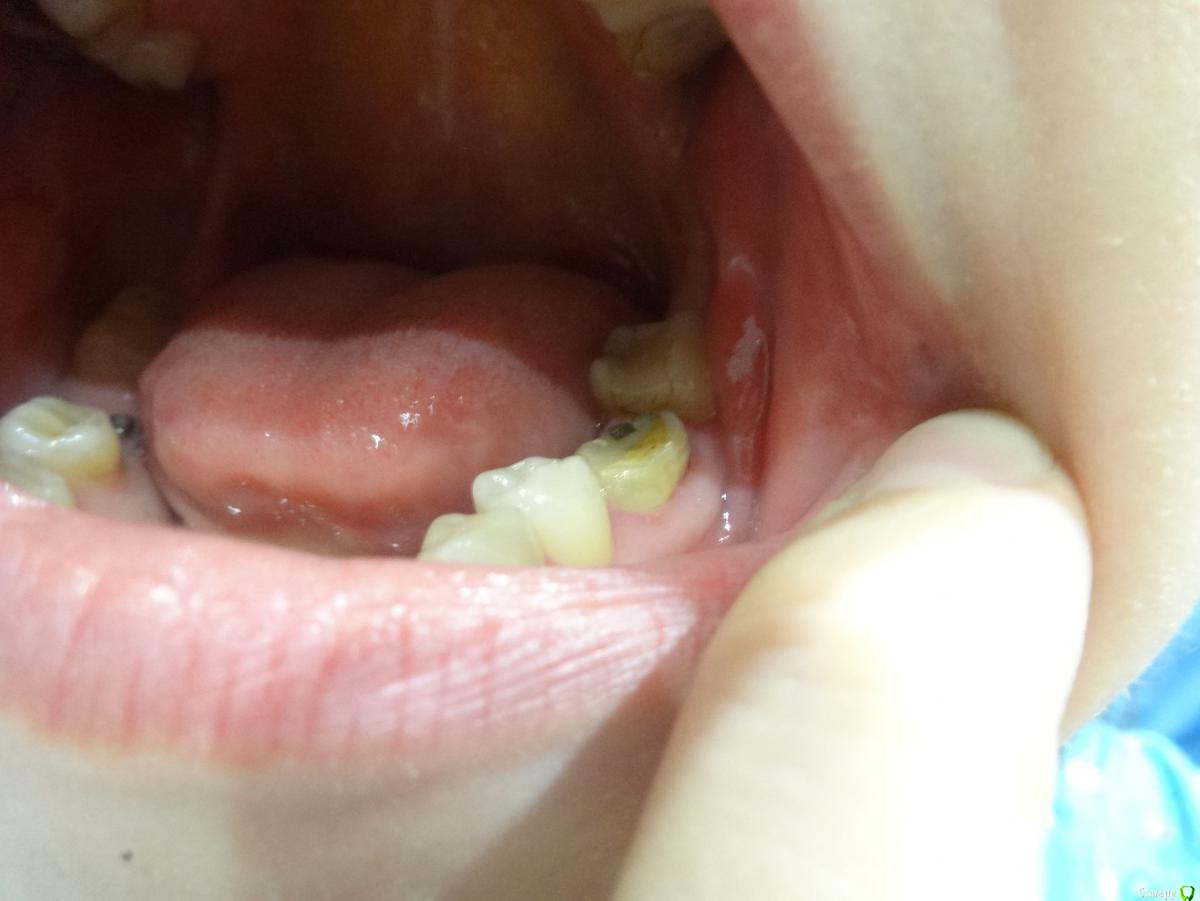

lepestochek Опубликовано 5 ноября, 2015 Поделиться Опубликовано 5 ноября, 2015 (изменено) Здравствуйте! Хотелось бы услышать профессиональную оценку по поводу жевательного зуба 36. Более 10 лет на нём стояла коронка. На снимке врач увидел воспаление у корня и предложил протезирование коронкой из диоксида циркония и, вероятно, вкладка( точно скажет на следующем приёме), предварительно пролечив каналы. После чего воспаление должно со временем исчезнуть. Коронку сняли( фото). На внутренней стороне нет стенки, поэтому хотелось бы знать надёжно ли будет предложенное лечение. А если и возможно, то нельзя ли металлокерамической коронкой накрыть? 15 зуб подготовили под культевую вкладку из кобальт хрома и коронки из диоксида циркония, так как металлокерамика сказали не будет держаться. И это немалые деньги. Ещё раз прошу, подскажите, стоит ли 36 зуб таких затрат? Спасибо. Изменено 5 ноября, 2015 пользователем lepestochek Ссылка на комментарий

4ebstom Опубликовано 6 ноября, 2015 Поделиться Опубликовано 6 ноября, 2015 36-печально,что нет язычной стенки зуба.Если восстанавливать-я бы кхс вкладка+цельная цирк.коронка. Ссылка на комментарий